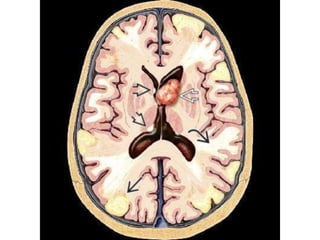

• #28 Axial graphic of typical brain involvement in tuberous sclerosis complex shows a giant cell astrocytoma in the left foramen of Monro, subependymal nodules , radial migration lines , and cortical/subcortical tubers .